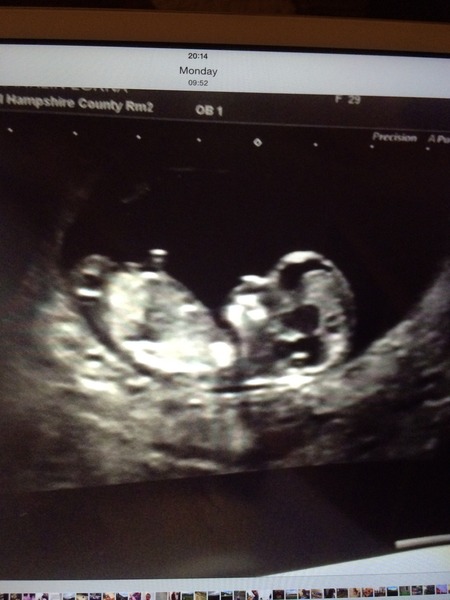

Here is my scan photo. Glad yours went well mascara I remember it was near mine :)